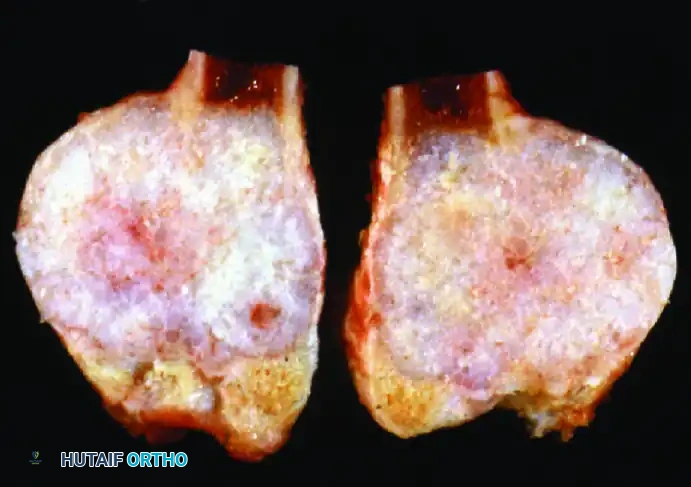

D: Gross pathological specimen sectioned longitudinally. Histological analysis confirmed a low-grade chondrosarcoma with negative surgical margins.

E: Postoperative radiograph demonstrating the complete primary resection of the proximal fibula. The patient required no adjuvant chemotherapy or radiation, and retained full function of the peroneal nerve.